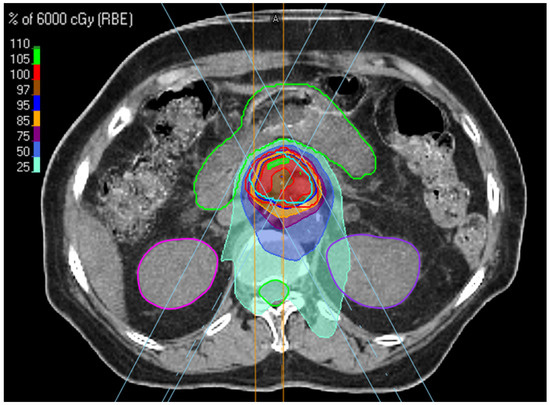

2.2. Treatment